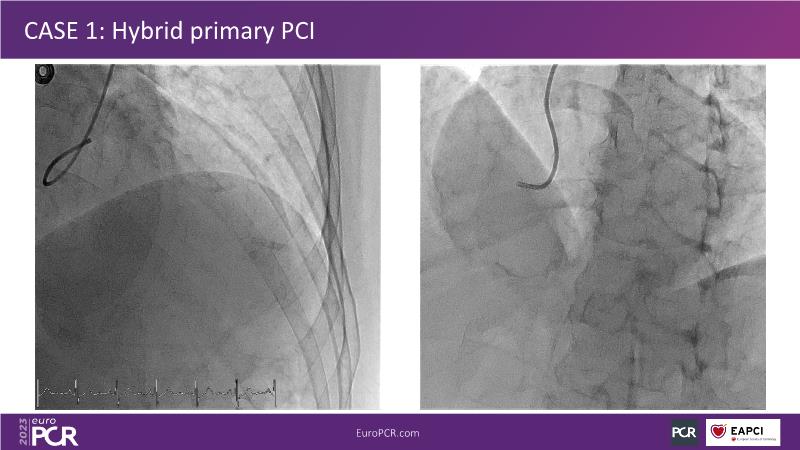

• To know why and how a fusion coating of DES+DCB stent platform is effective for the treatment of cardiovascular disease in diabetes mellitus patients via case presentations

• To understand why you can count on customised drug delivery platform of DES+DCB in complex settings with imaging-based evidence through case presentations